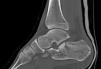

Mala consolidación tipo II: exostosis lateral prominente y artrosis subastragalina (fig. 9). Tratamiento mediante exostectomía lateral, tenólisis de peroneos y artrodesis subastragalina con injerto estructural en bloque (figs. 10 y 11).